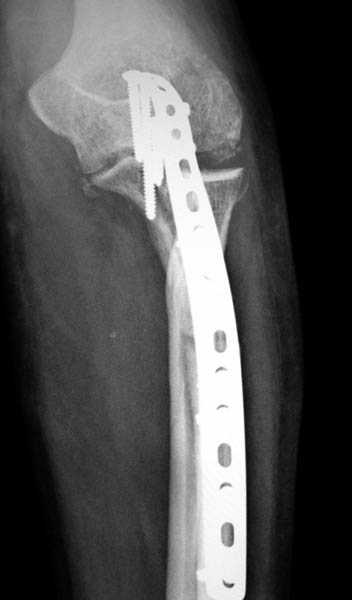

Для фиксации перелома локтевого отростка на сегодня множество преконтурных с блокирующими возможностями пластин.

Стабильную фиксацию, особенно при оскольчатых

переломах, можно добиться, применяя технику Bridge Plate, и за счет тех пластин, где имеется возможность проведения множественных шурупов (2.7 мм) проксимально.

Предложенные реконструктивные пластины в 3.5 мм

идеальны для фиксации при отрывном или флексионном

переломе, когда имеется большой фрагмент.

Здесь выставлены несколько случаев и варианты фиксации локтевого отростка, некоторые в комбинации с другими переломами.

1 вариант применен ACUMED локинг пластина

2 вариант

перелом локтевого отростка с переломом головки лучевой кости (использованы 2 мм шурупы)

3 вариант

перелом с capitelum humerus и проксимальной трети улна